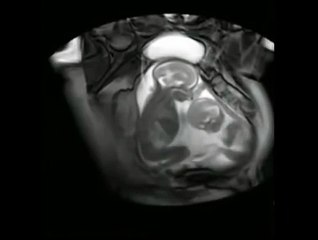

உங்க வீட்டு சண்டை இல்லை.. எங்க வீட்டு சண்டையும் இல்லை.. பக்கத்து br br வீட்டு சண்டையும் இல்லைbr Twin Sisters fighting in the during scan in br br China.